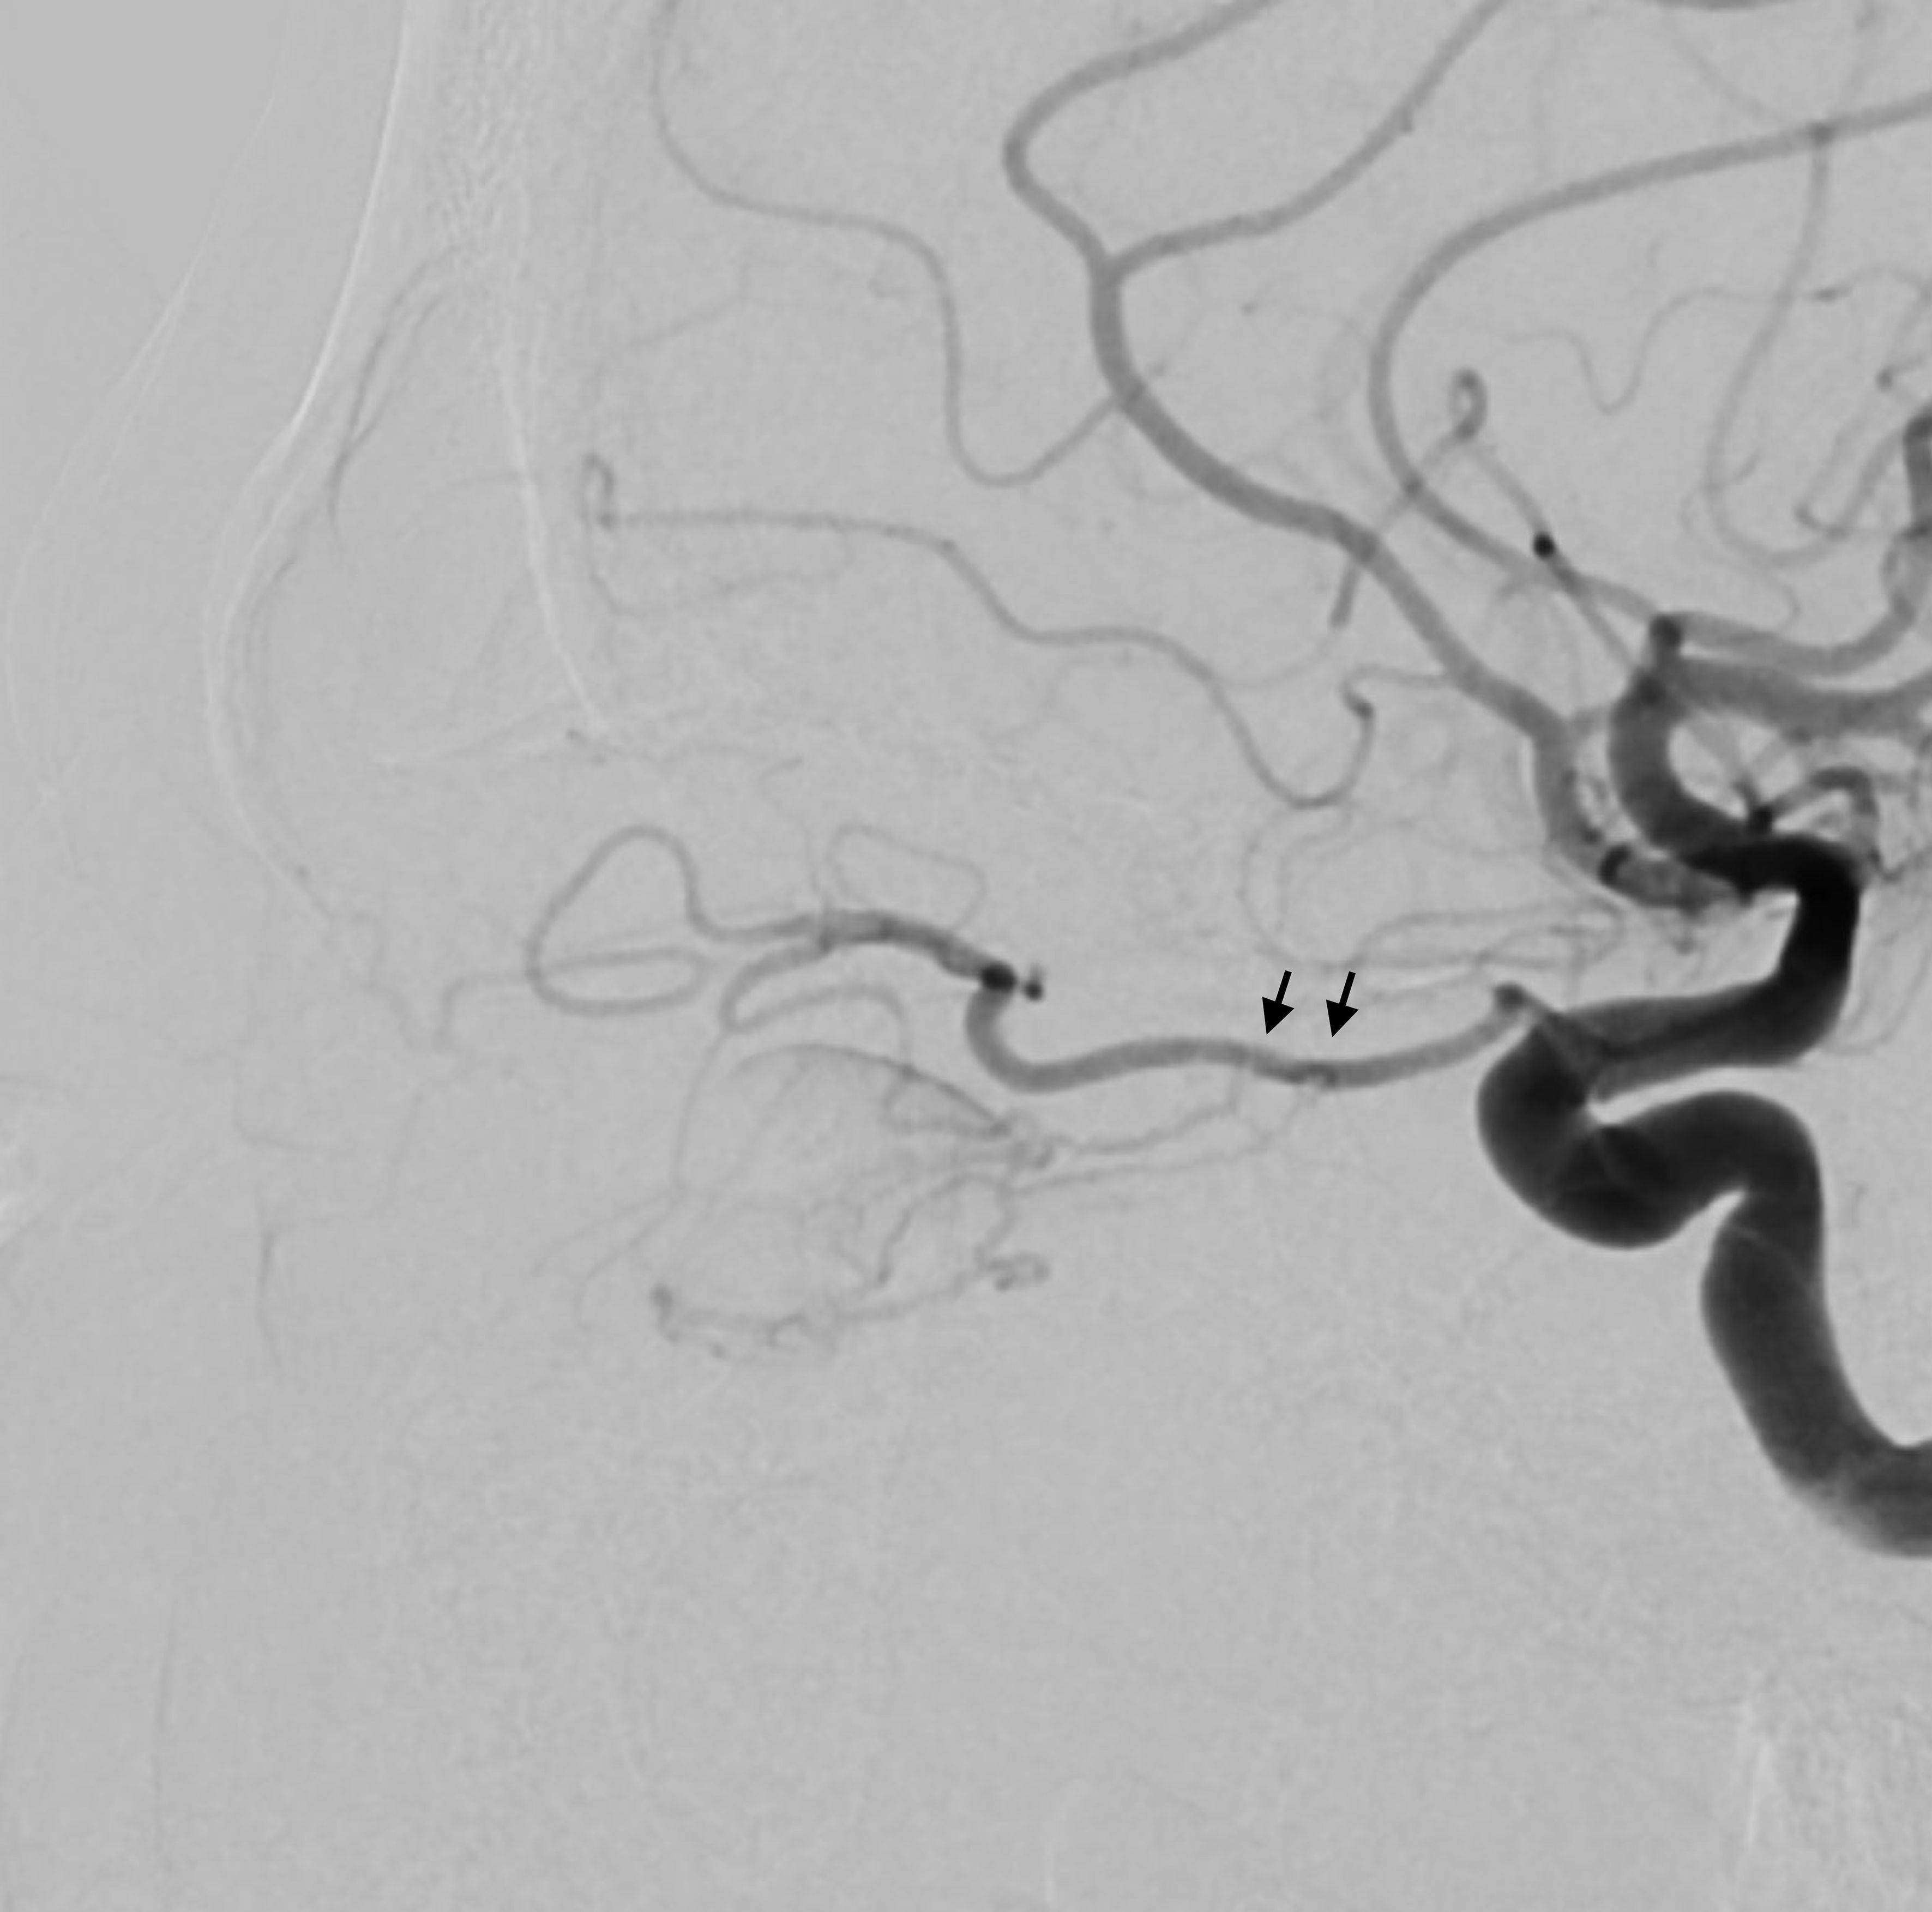

An angiogram showing blood vessels in a grayscale image, with a black arrow indicating a specific area of interest. Two circular objects are visible on the left side of the image.

Figure 5. Lateral view of the angiogram demonstrating a percutaneously placed catheter (arrow) in the dilated venous aneurysm of the fistula. There is contrast outflow superficially without direct connection to the cavernous sinus.

A multi-disciplinary surgical plan was developed. The patient underwent left medial orbital decompression to decompress the optic nerve, decongest the orbit, and provide access to the venous bulb of the fistula. This was followed immediately by cannulation of the venous anomaly in the operating room using a 5-French micropuncture sheath under direct intraoperative observation (Figure 5), followed by transfer to the fluoroscopy suite. With intraoperative angiography providing a “road map”, the venous outflow channel to the SOV was embolized with 20 coils, revealing a second outflow channel. The orbital catheter was manipulated and repositioned to access the second channel, which was then embolized with another 18 coils. At this point, the venous component was noted to have venous stasis (Figure 6), which would promote clotting followed by involution of the venous anomaly. The SOV was preserved and patent. Given the potential for a compartment syndrome, a lateral canthotomy and a cantholysis were performed preemptively to preserve normal intraocular and intraorbital pressure in the immediate post-operative period.